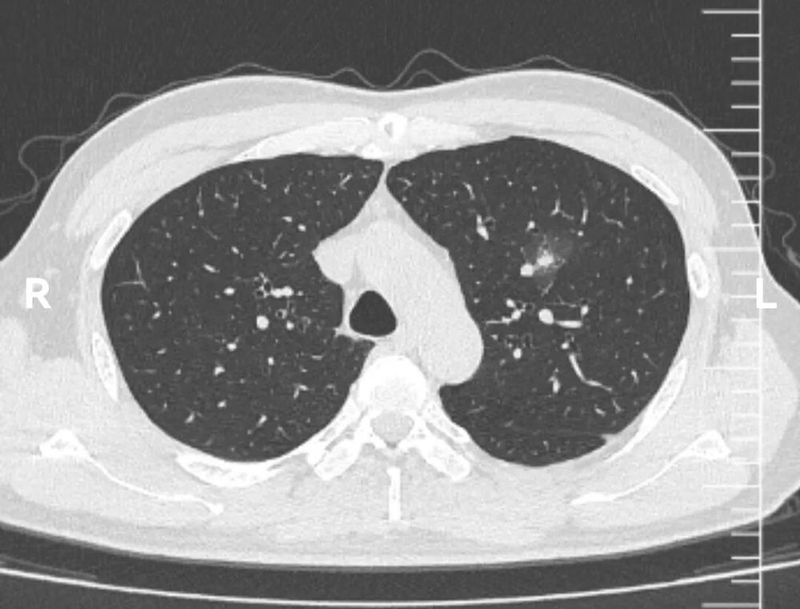

CT图像

这个左上肺混杂磨玻璃结节CT图像非常有特点,首先,磨玻璃成分为主,而且磨玻璃成分边界模糊不清。这本身就是炎症的典型表现。其次,实性成分的形态边界比较清楚,没有分叶、血管异常等形态。